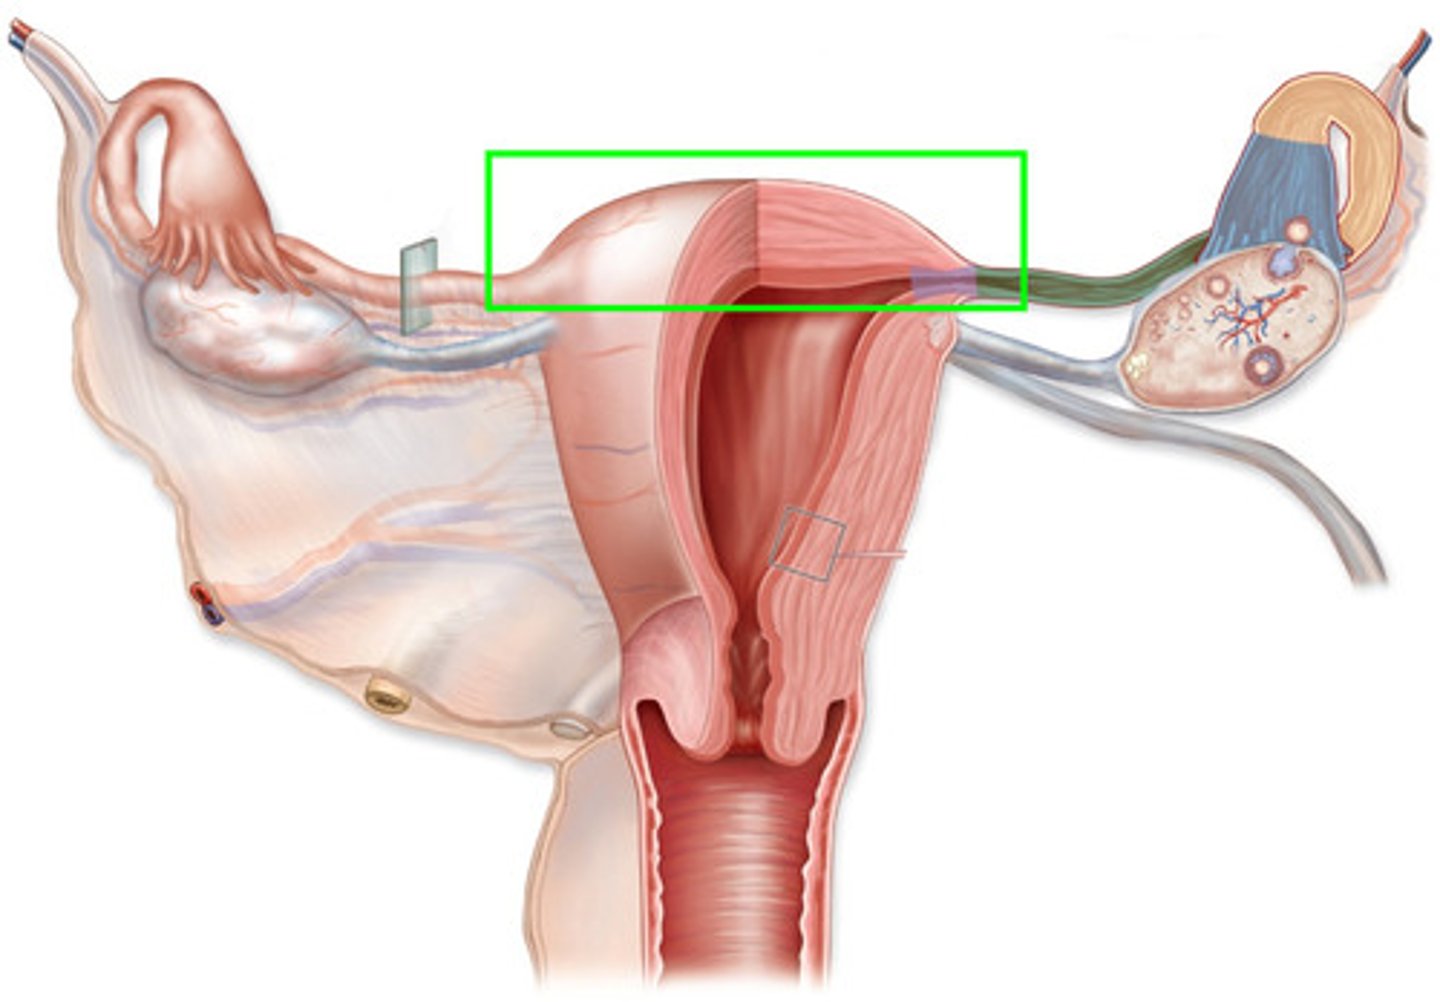

fundus of uterus

Most superior & widest portion of uterus, used to track fetal development based on position

What are common symptoms that arise from the fetus compressing abdominal organs?

shortness of breath, heartburn, reduced stomach capacity, issues moving chyme/feces